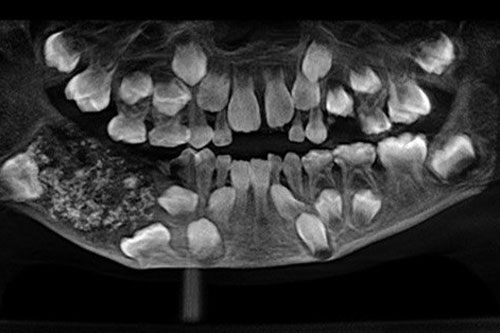

Hình ảnh chụp X-quang cho thấy một cậu bé 7 tuổi ở Ấn Độ có đến 526 cấu trúc giống răng lớn nhỏ “chen lấn” nhau trong hàm.